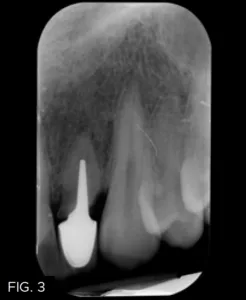

The patient returned six months later with the post on #10 decemented. A root fracture was visible both clinically and radiographically. (FIG. 3) The prognosis was deemed poor and options for the replacement of this tooth were once again discussed.

The periodontist extracted the failing #10, immediately placed a 4/3 x 15 mm endosseous implant (Biomet 3i), and performed a soft tissue augmentation procedure to achieve maximum gingival esthetics.6 With the healing cap in place, the clear aligners were fitted with a custom pontic to replace the extracted #10 for three to four months. Once the periodontist confirmed implant integration, impressions were taken to create a temporary crown on the implant. The surgeon then refined the soft tissue augmentation and the temporary crown was modified to ensure optimal esthetics (FIG. 4-5b).5,7

The healing time for the temporary crown was six months, during which time the patient was instructed to wear his aligners nightly. Once tissue healing was achieved (FIG. 6), the temporary crown was removed, and an implant transfer was placed and verified with a periapical radiograph. (FIG. 7)